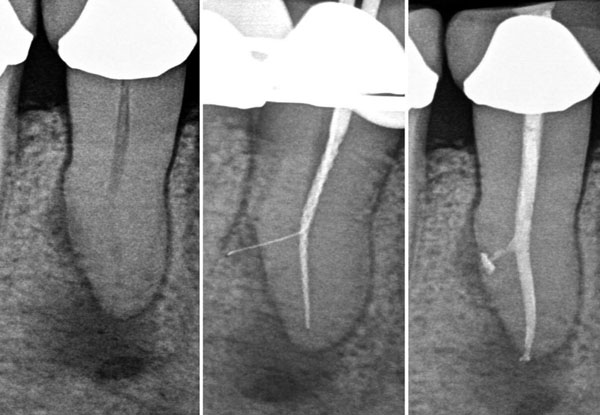

PROCEDURE :

Step 1

• Local Anesthesia is administered, after which Endodontist removes infection from the canals.

Step 2

• Cleaning and shaping of canals is carried out along with irrigation with sodium hypochlorite.

Step 3

• This protocol is followed till the root apex and ultimately the canal is sealed with gutta percha.